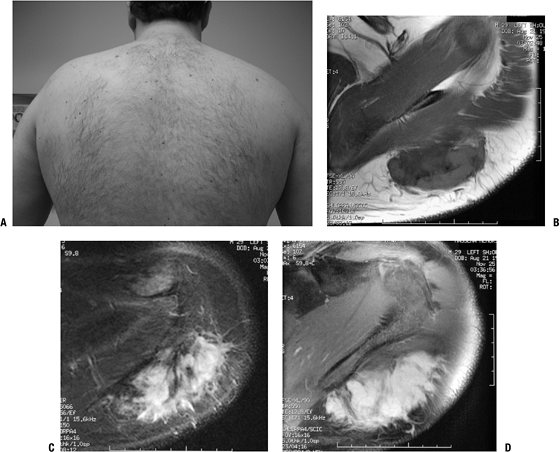

Low-cellularity collagenous tissue with intermixed elastic fibers (Fig. 11-8)

MRI may be highly suggestive (Fig. 11-9).

Fatty areas: bright areas on T1-weighted images, intermediate on T2-weighted images

-

Fibrous areas: similar to muscle

![]() |

Figure 11-8 (A) Elastofibroma composed of intertwining, swollen collagen and elastic fibers with fibroblasts. (B) Elastic fibers highlighted by EVG stain in elastofibroma.

Figure 11-9 (A)

The characteristic location for an elastofibroma is at the inferior

a heterogeneous subscapular soft tissue mass on T1-weighted (B) and proton density (C) axial images. -